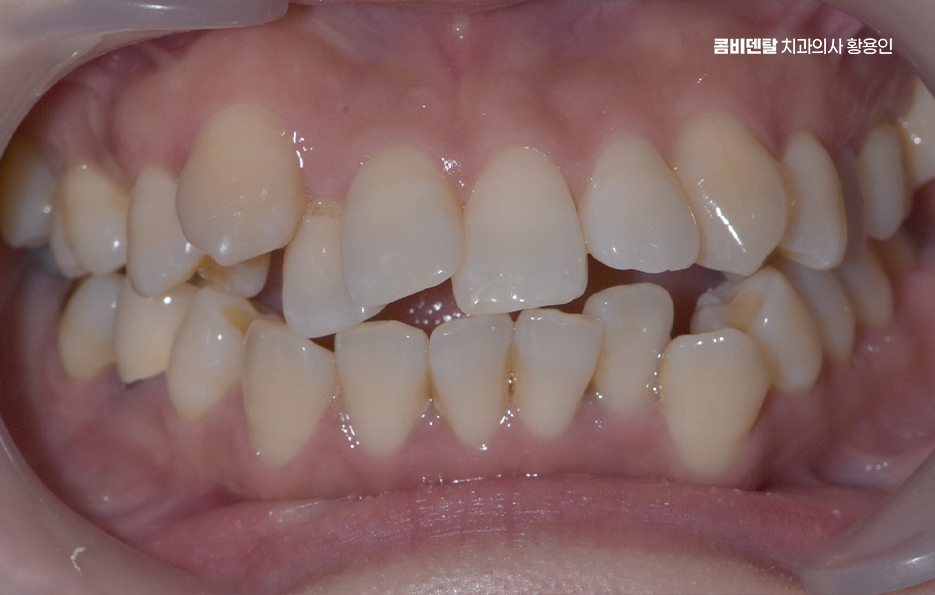

출처 아카이브 열기거울을 보다 보면 늘 시선이 먼저 가는 게 앞니였어요, 남들이 보기엔 별로 티 안 나는 거라고 생각하기도 했지만 항상 앞니가 조금 틀어져 있다는 걸 의식하게 됐고, 사진 찍을 때도 살짝 미소만 짓게 되는 이유가 그거였어요, 사실 예전부터 교정을 해야겠다는 생각은 있었지만 앞니만 살짝 신경 쓰이는 정도라서 큰 결심까지는 안 갔었고, 그냥 참고 살면 되지 뭐 이런 식으로 넘기곤 했는데, 어느 날 치과에 전반적인 치열이 생각보다 안 좋은 편이라고 말씀하시는 걸 듣고는 좀 충격을 받았어요, 제 눈에는 앞니만 문제였지 전체적인 교합이 그렇게 문제인 줄은 몰랐거든요. 정확한 상태를 알기 위해 정밀 검사를 받았는데, 앞니가 살짝 겹쳐 있는 건 물론이고 아래쪽 어금니는 바깥쪽으로 기울어져 있어서 씹는 힘이 한쪽으로만 가고 있고, 전반적으로 치아 배열이 삐뚤빼뚤하게 늘어선 상태라 기능적인 문제도 고민할 수 밖에 없었어요

이처럼 치아교정을 결심하게 되는 계기에는 유독 눈에 띄는 앞니 위주로 치료를 원하게 되는 경우도 많지만 디테일한 치료 계획을 세워보면 부정교합이나 얼굴형 변화 등에서도 생각보다 깊이 있게 신경써야 하는 경우도 많이 있는데요

치아가 가지런하지 않다는 건 단순히 보기 좋지 않다는 의미를 넘어서, 실제로는 씹는 기능, 발음, 턱관절, 그리고 구강 위생까지 다양한 부분에 영향을 주는 문제인데 이럴 때는 단순히 앞니 틀어짐 교정을 앞니만 고친다고 해결되는 게 아니고, 전체적인 치아 배열과 교합을 고려한 치아교정 계획이 필요할 수 있었어요

앞니 틀어짐 교정 앞니가 틀어져 있다는 건 그 앞니에만 문제가 있는 게 아니라는 걸 의미할 수 있는데 대부분은 전체적인 부정교합 속에 앞니 틀어짐이 같이 포함되어 있는 거예요.

예를 들어 송곳니가 제자리를 찾지 못해 앞으로 튀어나와 있거나, 소구치가 비틀어져 있으면 그 힘이 앞니로 전달되면서 앞니가 서로 겹치고 밀리는 형태가 되는데 즉, 보이는 앞니가 문제처럼 보일 뿐, 실은 그 뿌리를 뒤에서 밀어내는 힘들이 원인이 될 수 있기 때문에 앞니만 간단히 밀어넣는 식의 교정은 일시적인 변화만 줄 수 있고 전체 치열을 다 잡아줘야 안정적인 결과를 만들 수 있었어요.